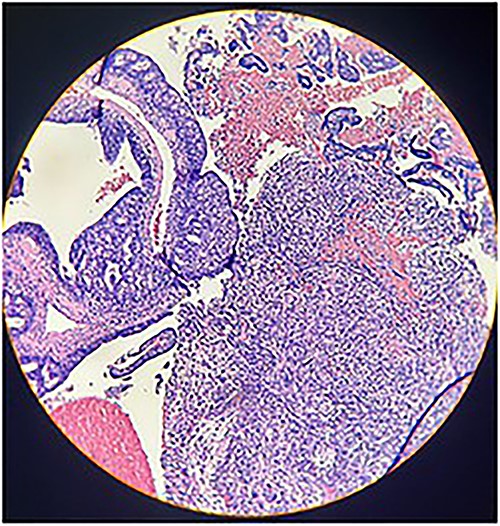

Macroscopically, an amorphous uterus weighing 397 g and measuring 12 × 9 × 7.5 cm with a brown serosa, and multinodular violaceous areas was examined. When incised, the endometrial cavity was occupied by a whitish polypoid mass of 8 × 5 cm which invaded the myometrium. In addition, multiple firm whitish nodules ~2 × 1.5 cm in diameter were identified. Bilateral ovaries and fallopian tubes appeared to be of normal morphology and size. Histologically, there was evidence of epithelial and sarcomatous components (Figs 1 and 2), and the epithelial component developed atypical glands (Fig. 3). The diagnosis of MMMT was given due to histologic findings.

Photomicrograph shows the presence of a malignant mixed tumor containing epithelial and sarcomatous components (H&E stain ×4).